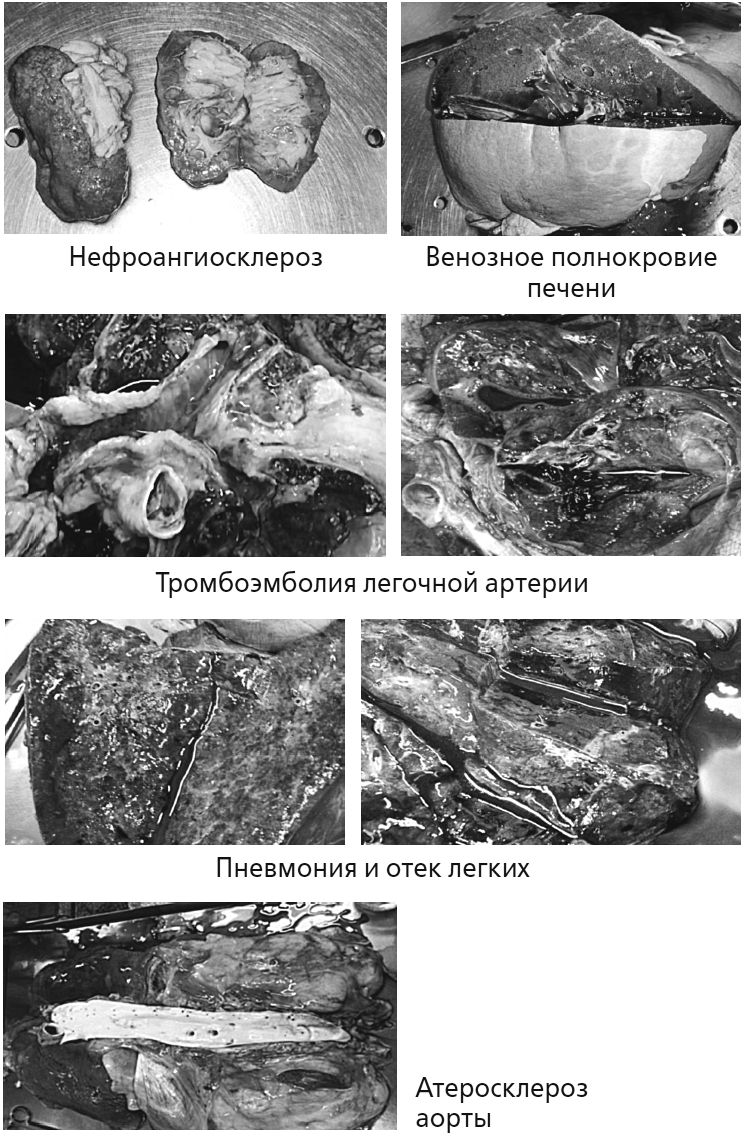

Патологоанатомический диагноз:

Осн.: ИБС: мелкоочаговый кардиосклероз.

Фон: Артериальная гипертензия (масса сердца – 480 г, толщина стенки левого желудочка – 1,9 см).

Атеросклероз аорты и ее магистральных ветвей. Нефроангиосклероз.

Осл.: Фибрилляция предсердий, постоянная форма (клинически). Тромбоэмболия сегментарных и более мелких ветвей правой легочной артерии с развитием инфарктной пневмонии в нижней доле правого легкого. Хроническое общее венозное полнокровие. Острые эрозии желудка. Отек легких. Отек головного мозга.

Соп.: ХОБЛ: хронический обструктивный бронхит.